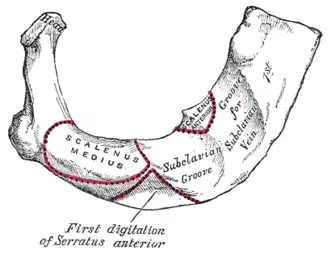

Vue latérale.

Vue latérale. Vue antérieure

Vue antérieure Insertion costale du muscle subclavier (subclavian groove)